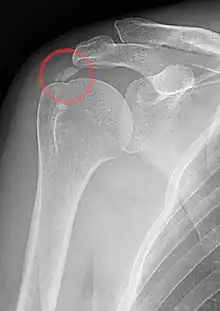

An x-ray showing calcific deposits in the area of the tendons of the rotator cuff muscles

Calcific tendinitis is typically diagnosed by physical examination and X-ray imaging.[1] During the formative phase, X-ray images typically reveal calcium deposits with uniform density and a clear margin.[1] In the more painful resorptive phase, deposits instead appear cloudy and with unclear margins.[1] By arthroscopy, formative stage deposits appear crystalline and chalk-like, while resorptive stage deposits appear smooth resembling toothpaste.[1] Ultrasound is also used to locate and assess calcium deposits. In the formative stage, deposits are hyperechoic and arc-shaped; in the resorptive stage deposits are less echogenic and appear fragmented.[1][3]